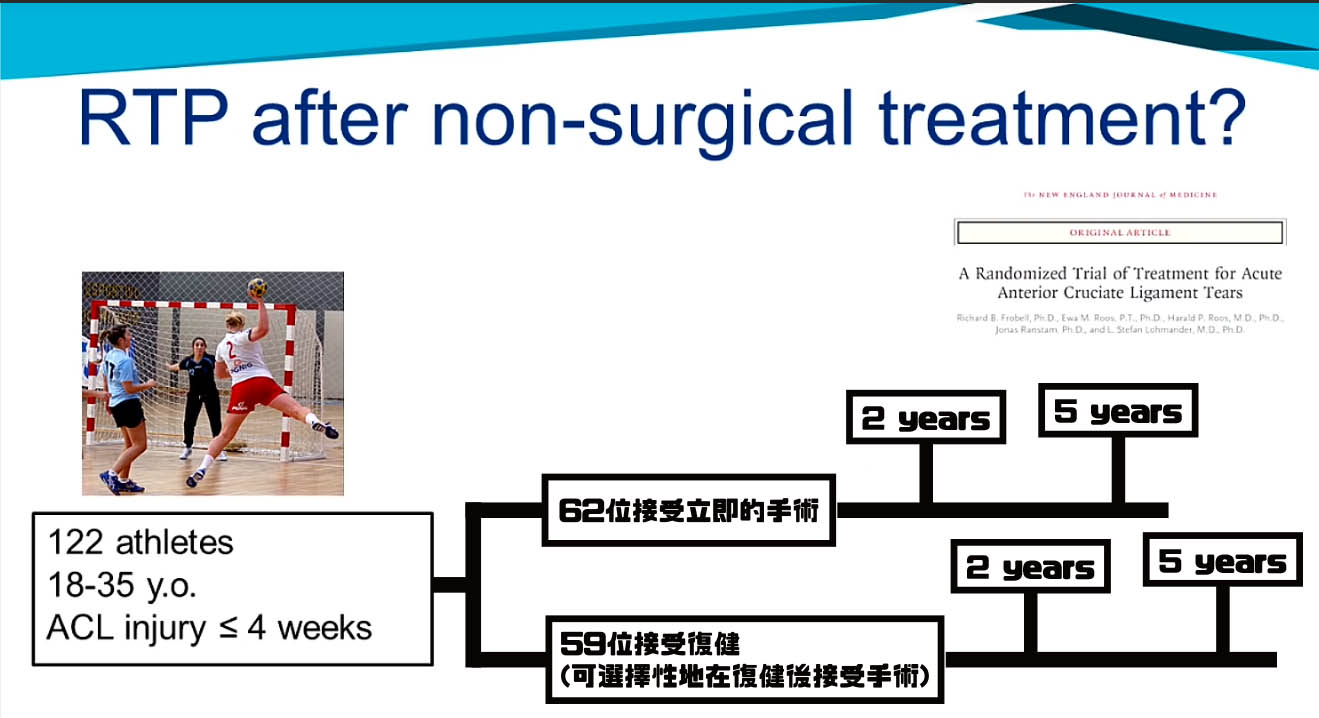

回到賽場return To Play Aclr 專題篇 二 By Sik Hon Medium